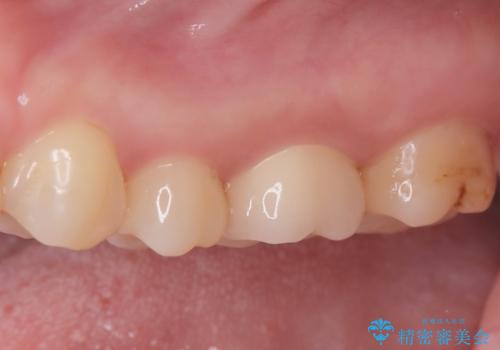

2回で完了した奥歯のセラミック修復

- 奥歯の虫歯治療を主訴にご来院されました。患者様から「できるだけ通院回数を少なく、早く治療を終わらせたい」というご要望があったため、短期間での完了を目指し、セラミックインレー(詰め物)とセラミッククラウン(被せ物)を併用する治療計画を立案しました。治療は精密機器を活用し、2回の来院で最終的なセラミック修復物を装着することを目指します。

今回の治療では、虫歯の大きさや深さに応じて、異なるセラミック修復法を適用しました。

比較的軽度な虫歯には、セラミックインレー(詰め物)で対応し、健全な歯質を最大限に残しました。

進行した虫歯や歯の強度が低下している歯には、セラミッククラウン(被せ物)を選択し、歯全体を保護することで破折を防ぎました。

短期間での治療を可能にしつつ、天然歯と見分けがつかない審美性と、長期的に安定する機能性を兼ね備えたセラミック修復を実現しました。